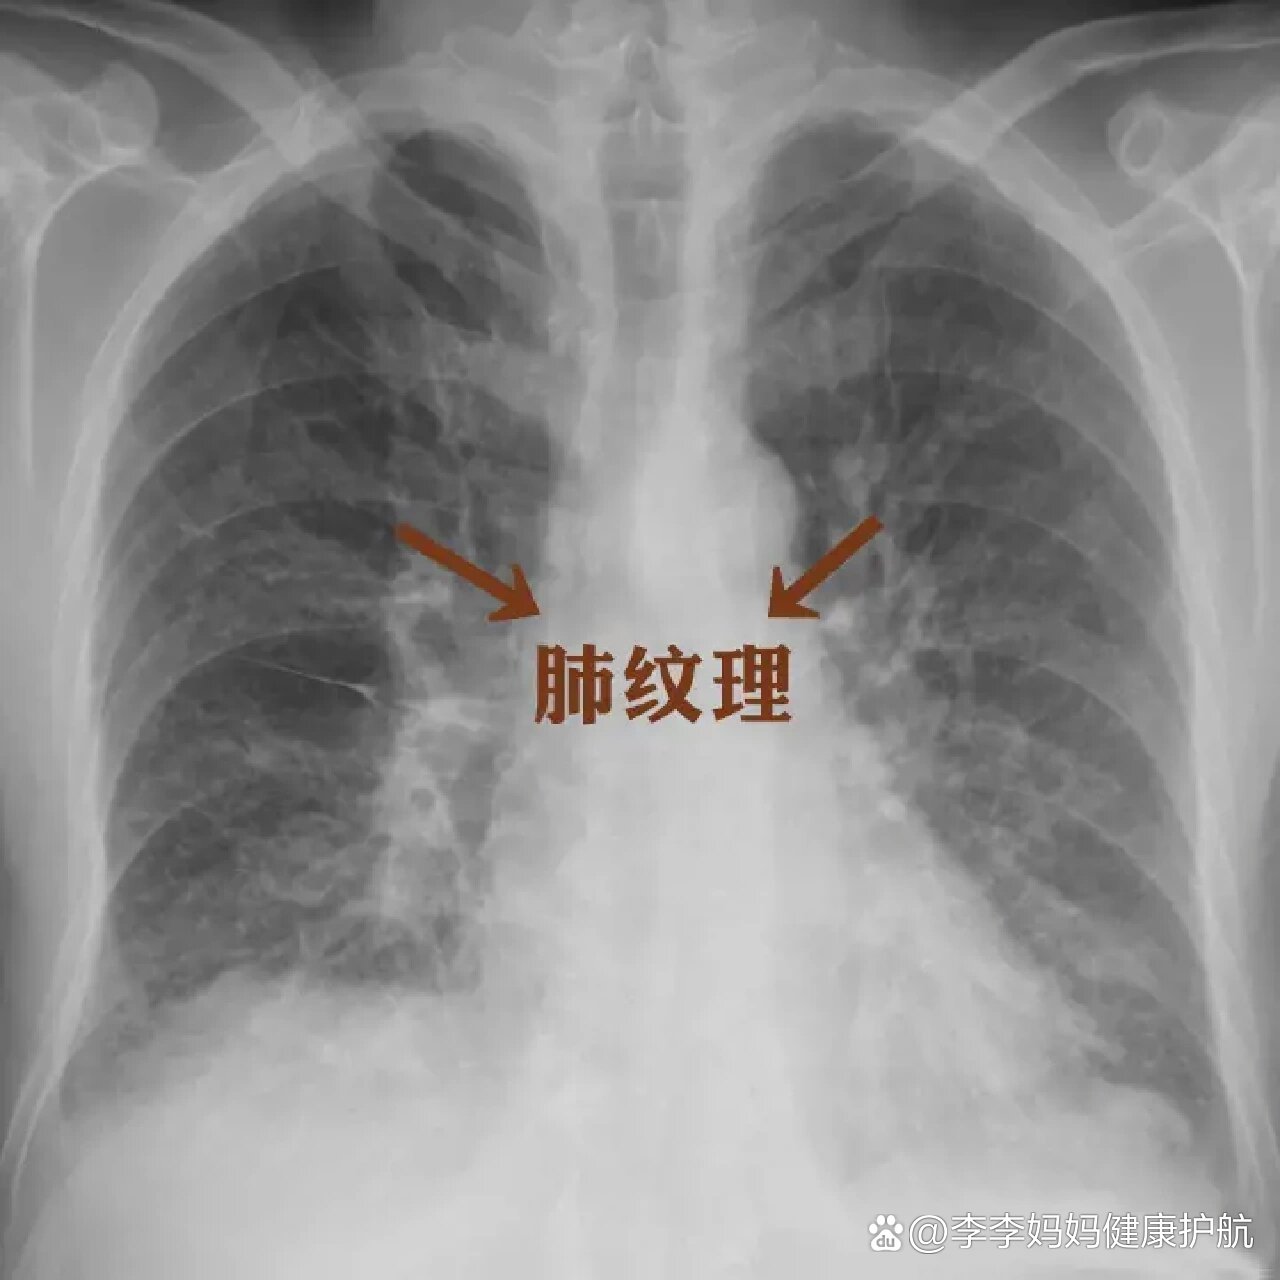

再讲讲胸片里面的肺纹理增粗和斑片影

1,纹理增粗 肺部纹理增粗往往提示支气管及其周围组织存在慢性炎症